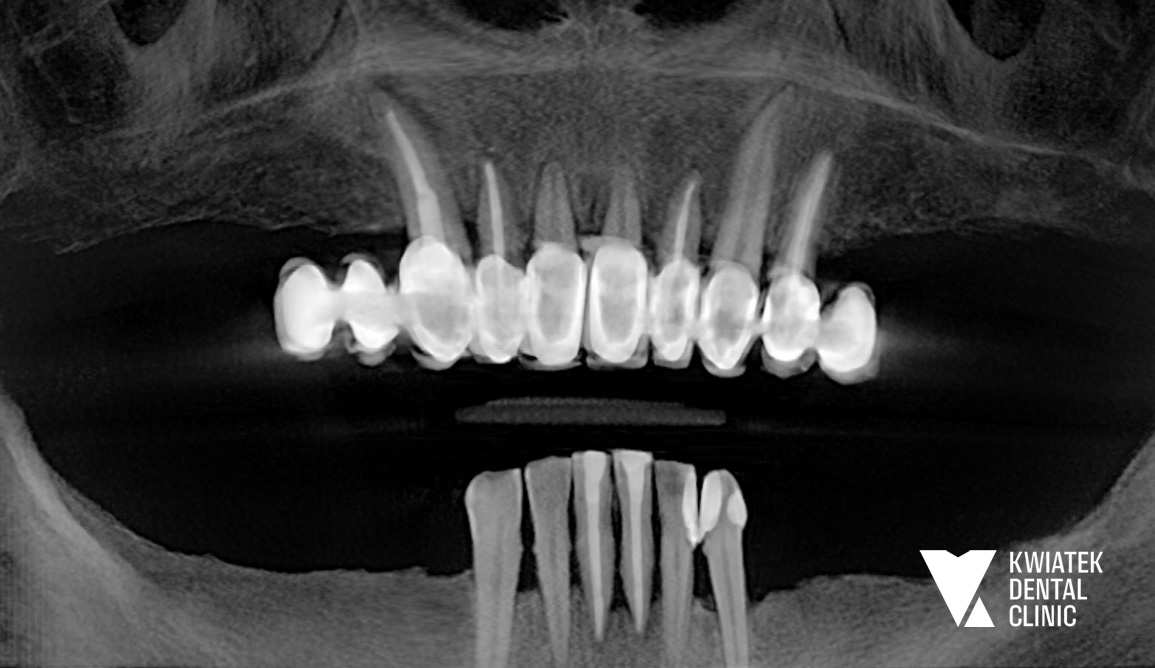

Luksus dyskretnej ortodoncji oparty na zaawansowanej technologii nakładkowej

Pacjentka zgłosiła się do kliniki z potrzebą kompleksowej poprawy zarówno funkcji zgryzu, jak i estetyki uśmiechu. W badaniu stwierdzono zgryz krzyżowy, stłoczenia zębów oraz liczne problemy wymagające leczenia zachowawczego i protetycznego, co wymagało wieloetapowego, interdyscyplinarnego podejścia. Terapię poprzedziło staranne przygotowanie jamy ustnej obejmujące ekstrakcję zębów mądrości, profesjonalną higienizację oraz odbudowę osłabionych struktur. Następnie wdrożono zaawansowane leczenie ortodontyczne z wykorzystaniem nowoczesnego systemu nakładkowego. Rezultatem jest harmonijny, stabilny zgryz, idealnie ukształtowane łuki zębowe oraz wyraźnie odmłodzony, jasny uśmiech, podkreślony profesjonalnym wybielaniem.